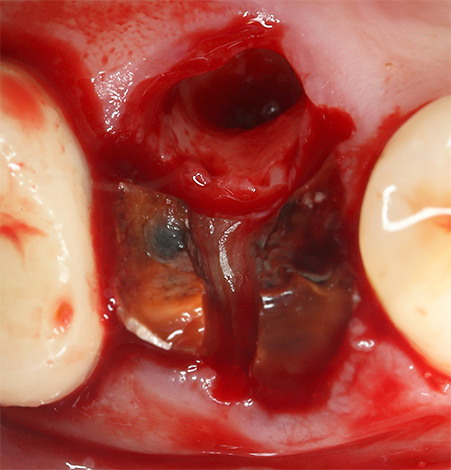

- Cirurgia traumática.

- Empurrar profundamente o poço do instrumento com pedaços de tecido cariado infectado em um dente ou placa dentária removidos.

- Violação da integridade dos ossos dos alvéolos, deixando bordas agudas e feridas na gengiva.

- Sangramento prolongado do buraco.

- A ruptura de um coágulo sanguíneo ou a sua ausência no buraco.